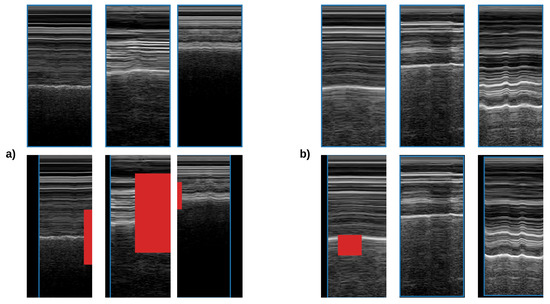

For data augmentation, we used random erasing [18] and random affine transformations (rotation, translation, and scaling), see Figure 5. The probability of the transforms was set equally to 0.5 . Rotation ranged between [ 10 , 10 ] degrees and horizontal translation between [ 0.1 , 0.1 ] of the image height; vertical translation ranged between [ 0.1 , 0.1 ] of the image width, and size scales ranged from 0.9 to 1.1 of the original size. Random erasing removed rectangular areas (pixels values set to 0) between [ 0.05 , 0.33 ] of the image area.

Figure 5. Dataset augmentation for M-mode classification. In the top row, we can observe original samples from the dataset, and in the bottom row, we can see augmented samples. Blue outlines the original image. Red represents randomly erased areas. (a) Examples of lung sliding presence; (b) examples of lung sliding absence.